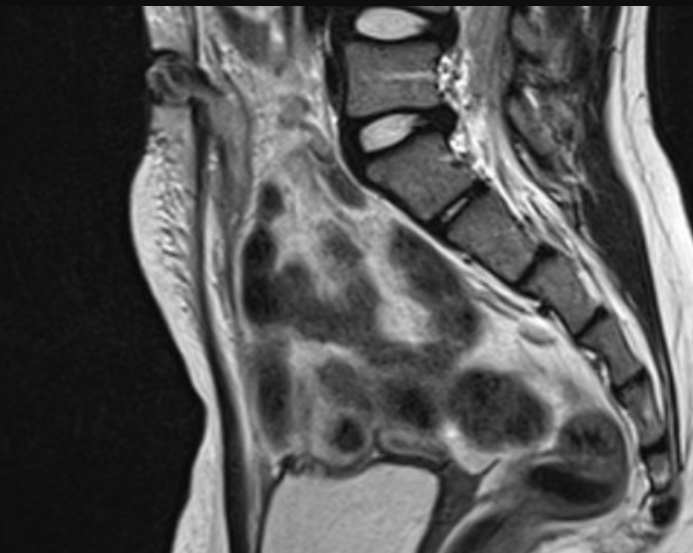

Kyste de l’Ouraque

- Deuxième plus fréquent (30%)